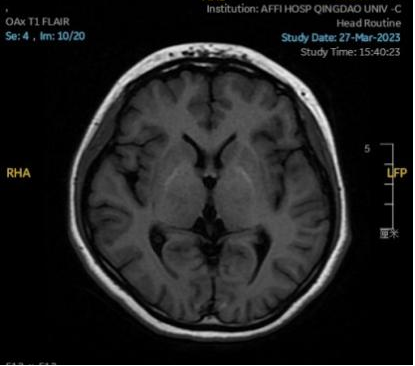

2023.03.27颅脑MR平扫示双侧基底节区及桥脑异常信号,考虑渗透性脱髓鞘综合征,较前范围略减小,请结合临床,见图4。

图4 2023.03.27双侧基底节区及桥脑见对称性片样长T1长T2信号,FLAIR呈高信号,较2023-02-24MR所示范围减小。脑室、脑池、脑沟、脑裂未见明显异常,中线结构居中。